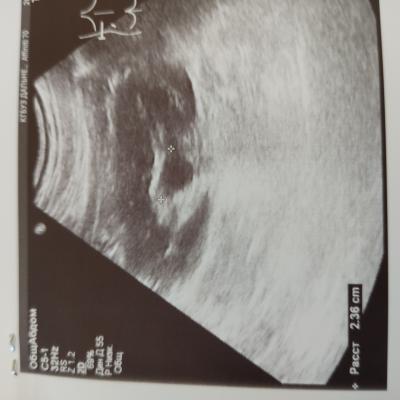

Дд. Помогите расшифровать УЗИ. Камень в почке, ужасные боли. Что можно сделать, чтоб облегчить их и ускорить выход камня? И выйдет ли каиень такого размера? Спасибо

Вам нужно начать с визита к врачу урологу на очный прием. Пройти обследование. Возможно потребуется выполнение компьютерной томографии для точной диагностики и точного выявления локализации камня и его размера. Без обследования, в первую очередь компьютерной томографии, принять решение о возможности или невозможности самостоятельного отхождения камня невозможно.